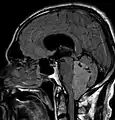

Les épendymomes supratentoriels (SE) représentent entre 40% et 60% des tumeurs intracrâniennes. Localisées au niveau supratentoriel, ces tumeurs apparaissent comme des grosseurs peu homogènes, présentant des zones kystiques, des calcifications mais également des zones hémorragiques et nécrosées.

Aspect radiologique à l’IRM en séquence T1 après injection de Gadolinium d’un épendymome supratentoriel, caractérisé par une lésion bien délimitée du lobe frontal gauche avec prise de contraste hétérogène et des zones de nécrose.

Épendymomes de la fosse postérieure

Les épendymomes localisés dans la fosse postérieure (PF) sont des tumeurs radiologiquement homogènes et bien délimitées, avec des remaniements hémorragiques et d'éventuelles taches de calcification montrant une prise de contraste variable due à la nécrose et à la formation de kystes. Ces tumeurs peuvent être localisées à l'intérieur du quatrième ventricule avec une expansion latérale possible à travers les foramens de Luschka ou le foramen de Magendie. Les épendymomes PF peuvent être divisés en deux sous-groupes en fonction de leur profil épigénétique : les PF de groupe A (PFA) et les PF de groupe B (PFB) [11].